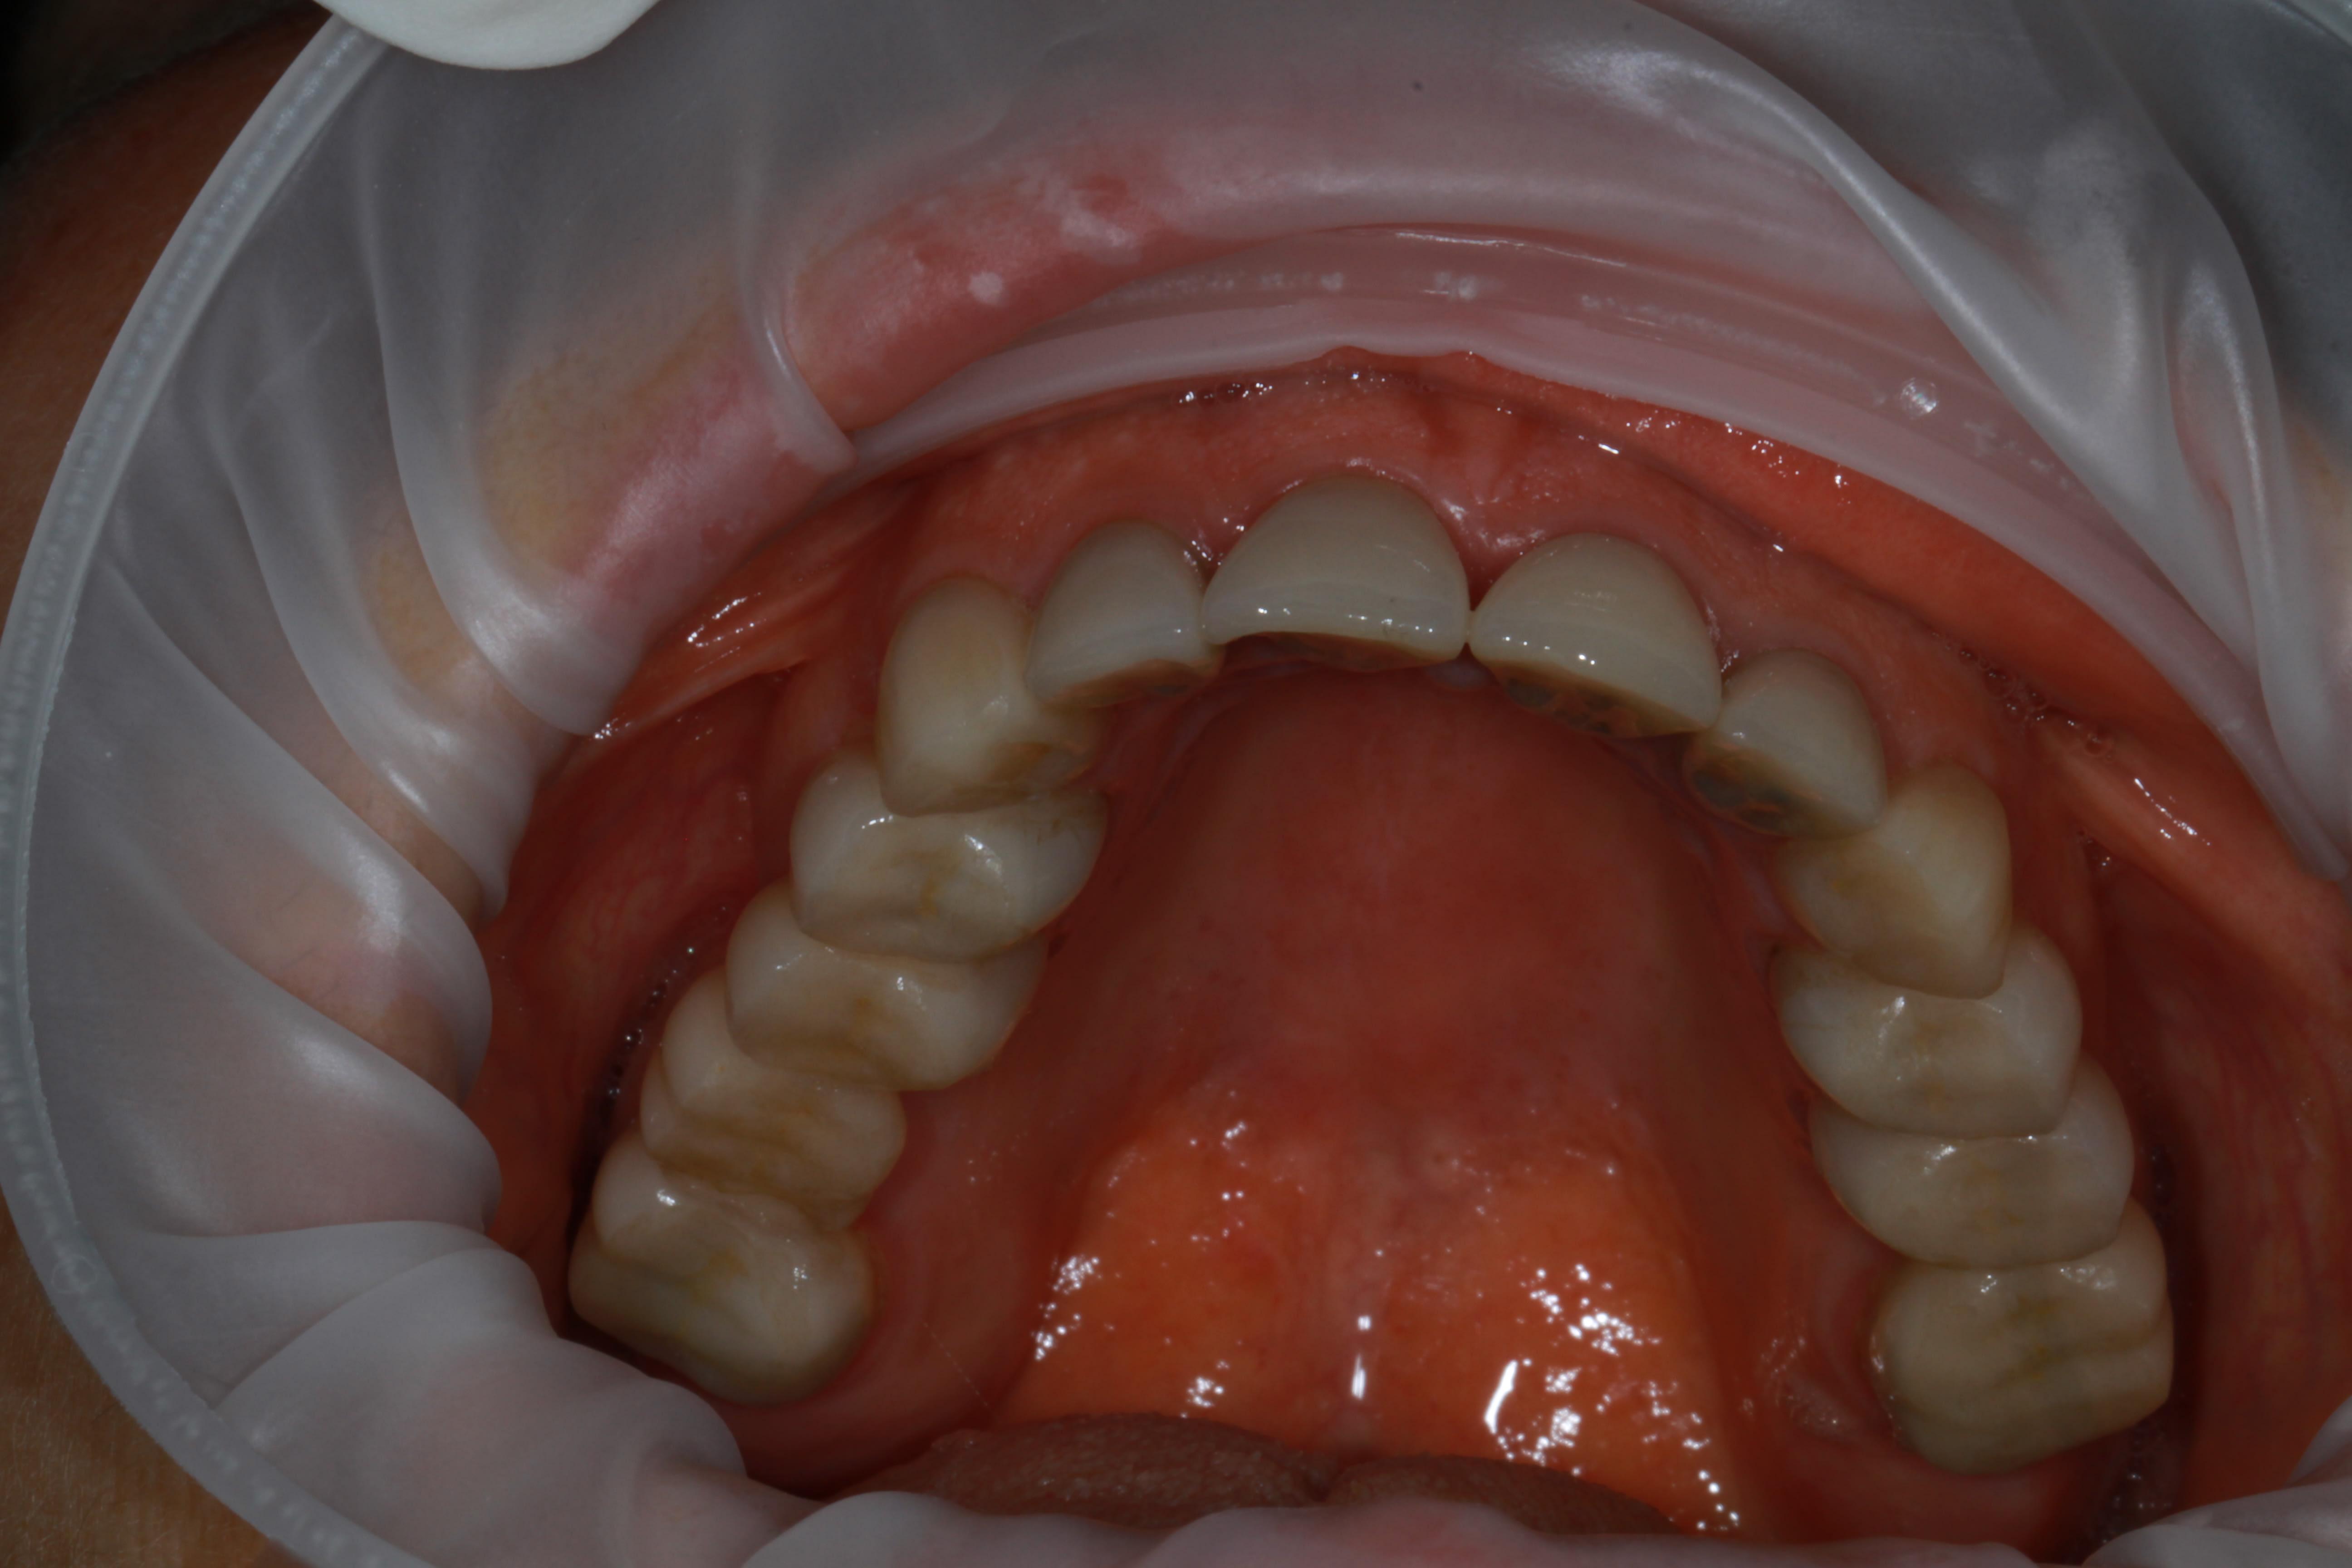

contrôle ce jour...

On reste dans le cahier des charges du panier CMU, et non y'a presque plus rien de vital, et pour certaines il a fallu faire de l'élongation et de la reprise endo gratis. C'est tout IC et CCM scellé à l'ancienne.

Et l'organisation c'est simple: mois d'Aout, fait 40° à l'ombre, pas un chat à l'horizon, donc il a bien voulu me tenir compagnie scotché au fauteuil toute la journée 1X par semaine.... le pauvre, il en a chier